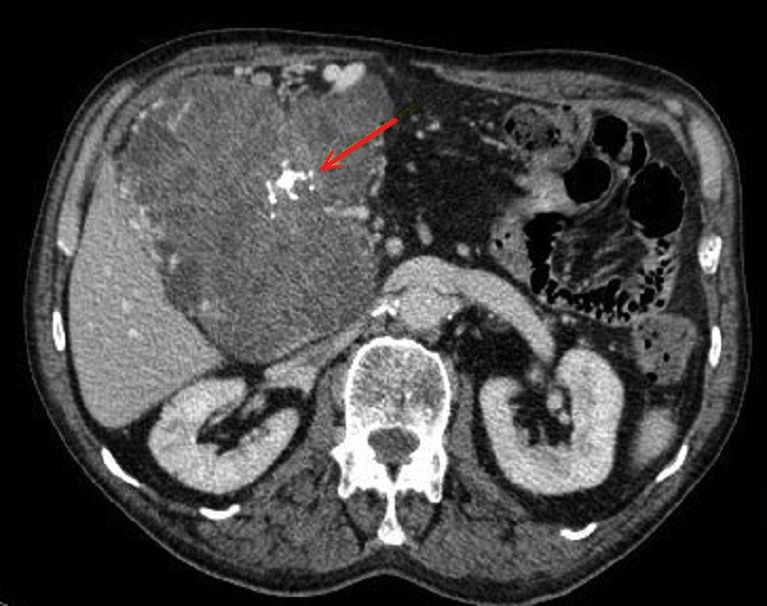

Image radiologique d'une cystadenome sereux

multikystique ismique du pancreas . Les cloisons (

septa ) interne et une partie de contour du tumeur

deviennent hyperdense de nette apres injection de

contrast iode intraveineuse ( signe de rehaussement

) . Coupe TDM plus C+ iode |

Image radiologique TDM d'une cystadenome

sereux macrokystique avec aspect lesionaire de kyste

hypodensite a grand taille de plus> 2cm situe au

queue du pancreas . Coupe TDM axiale n'a pas de

contrast intraveineuse |